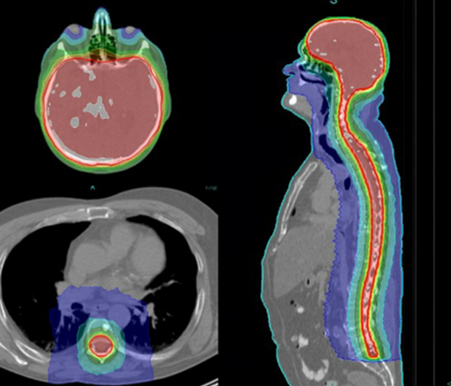

特長3

135 cm までつなぎ目の無い照射が可能

らせん状に回転しながら放射線を照射する独自の技術により、頭頸部から骨盤までなどの長い範囲へ一括照射が可能です。これにより、広範囲にわたる腫瘍や複数の腫瘍を1回の治療で均一にカバーすることができ、従来のように複数の照射野を組み合わせる必要がありません。その結果、線量のムラや接合部のリスクが減り、治療精度が向上します。また、治療時間の短縮にもつながり、患者様の身体的・心理的な負担を軽減することにつながります。